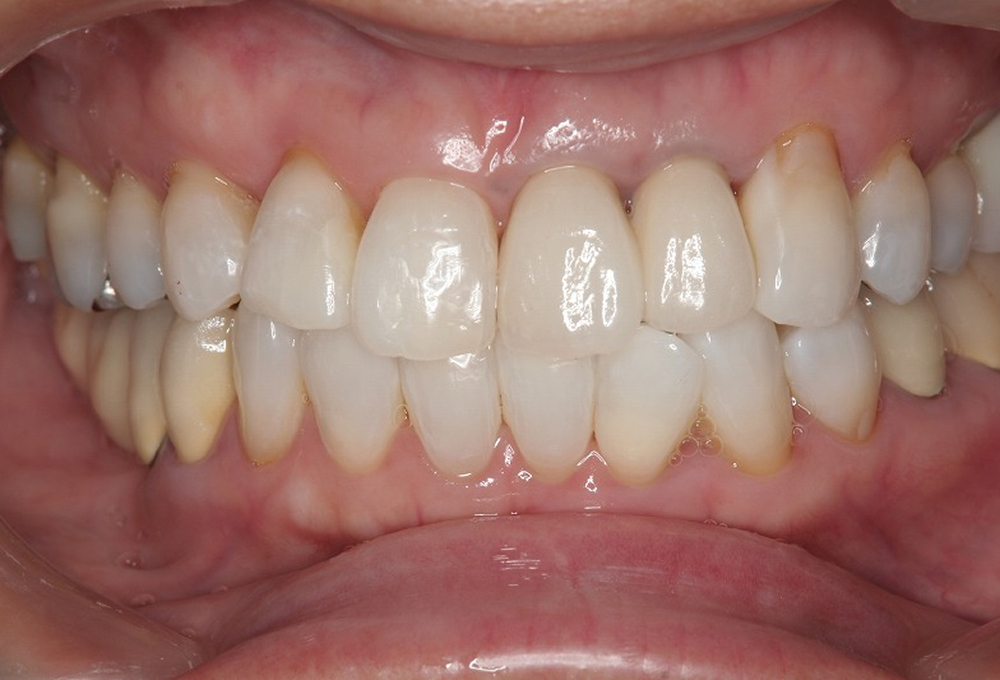

⑤矯正後補綴